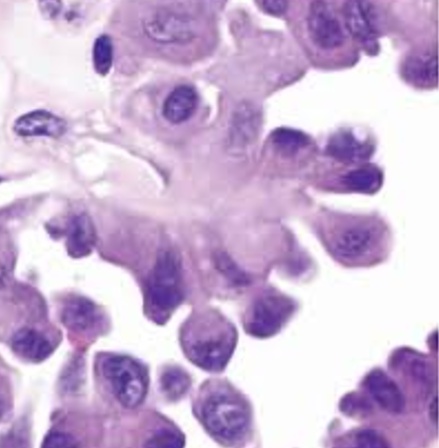

Pap smears. A‚ Normal. Large‚ flat cells with small nuclei. B‚ Dysplasia. Large‚ dark nuclei indicate damaged DNA; cytoplasmic halo indicates human papillomavirus (HPV) effect. C‚ Malignant. Compact cells with huge‚ irregular‚ dark nuclei indicate malignancy.

_Koilocytes (seen in all HPV related diseases) are seen beginning at the basal layer and extending outward. These are cells with a clear halo surrounding hyperchromatic, atypical nuclei. Increased mitotic activity.

_Histologically, condylomas associated with HPV are characterized by koilocytes with “raisin-like” nuclei surrounded by a halo.

High mag: koilocytes, raisin like nucleus